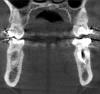

Oleg-Gru Опубликовано 8 апреля, 2013 Поделиться Опубликовано 8 апреля, 2013 (изменено) Здравствуйте! Полтора года назад был пролечен 36 зуб, закрыта старая перфорация коронковой части, пройдены каналы, сверху накрыто МК. На данный момент видимого ухудшения состояния этого зуба нет. Месяц назад, по ортодонтическим причинам, было сделано КТ. Интересует текущее состояние шестерки.Как вы думаете, каков ресурс у этого зуба? Пару-тройку лет протянет? Заранее благодарен! Изменено 8 апреля, 2013 пользователем Oleg-Gru Ссылка на комментарий

Oleg-Gru Опубликовано 10 апреля, 2013 Автор Поделиться Опубликовано 10 апреля, 2013 дело осложняется тем, что по окончании орт. лечения, скорее всего, придется менять коронки. И тогда встанет резонный вопрос: менять коронку на новую или не тратить деньги зря, удалять проблемный зуб и ставить имплант. Хотя, эта перспектива не ближайшего года, как минимум. Ссылка на комментарий

Oleg-Gru Опубликовано 10 апреля, 2013 Автор Поделиться Опубликовано 10 апреля, 2013 Вот еще картинки. http://img131.imagevenue.com/loc15/th_583456185_Snap2013_04_10at12.47.59_122_15lo.jpg http://img12.imagevenue.com/loc254/th_583457617_Snap2013_04_10at12.48.20_122_254lo.jpg http://img296.imagevenue.com/loc235/th_583458809_Snap2013_04_10at12.48.51_122_235lo.jpghttp://img187.imagevenue.com/loc397/th_583459766_Snap2013_04_10at12.50.16_122_397lo.jpg http://img274.imagevenue.com/loc159/th_583460103_Snap2013_04_10at12.50.37_122_159lo.jpg http://img41.imagevenue.com/loc73/th_583461588_Snap2013_04_10at12.50.52_122_73lo.jpghttp://img172.imagevenue.com/loc35/th_583462561_Snap2013_04_10at12.51.09_122_35lo.jpg http://img148.imagevenue.com/loc160/th_583464378_Snap2013_04_10at12.51.31_122_160lo.jpg http://img180.imagevenue.com/loc881/th_583465278_Snap2013_04_10at12.51.50_122_881lo.jpghttp://img267.imagevenue.com/loc241/th_583467842_Snap2013_04_10at12.52.12_122_241lo.jpg http://img284.imagevenue.com/loc186/th_583468956_Snap2013_04_10at12.54.07_122_186lo.jpg http://img281.imagevenue.com/loc559/th_583469358_Snap2013_04_10at12.54.33_122_559lo.jpg Ссылка на комментарий